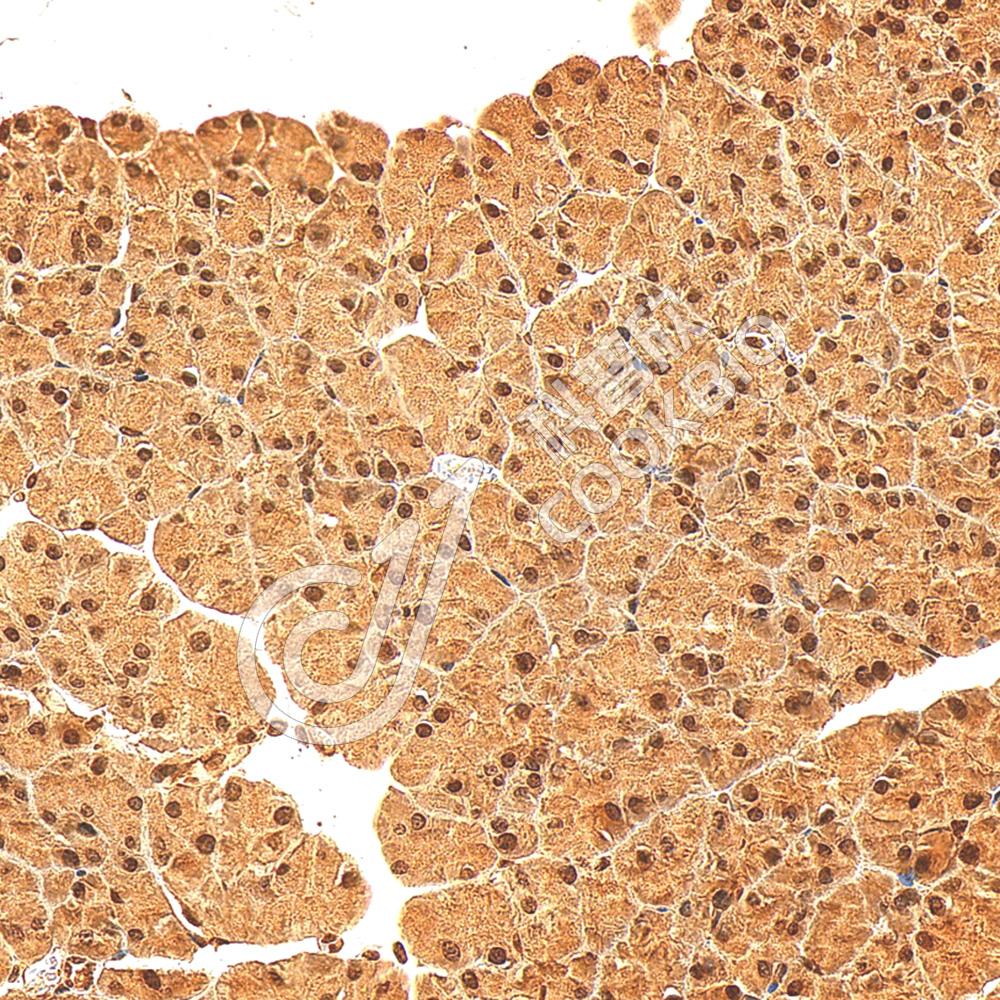

IHC检测IBTK蛋白(货号 K1343599).

样品: 大鼠胸腺, 4%多聚甲醛 (货号KSG1101) 固定12-24小时.

抗原修复: 柠檬酸抗原修复液(干粉, pH 6.0) (KSG1201), 98℃, 20分钟.

—抗: 1: 1200稀释, 4℃ 孵育过夜.

二抗: S-vision免疫组化多聚二抗(山羊抗兔),即用型 (货号KB3906), 室温孵育20分钟.